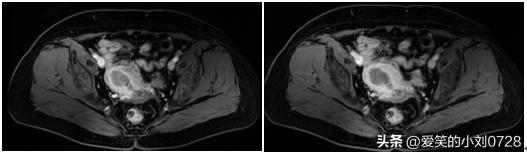

入院后给阿姨安排了盆腔的MR(核磁共振)和上下腹部的CT,明确有无远处的转移或者淋巴结的转移,和进行其他手术之前应该行的化验检查,幸运的是,仅仅发现阿姨宫腔里有病灶,在其他地方并没有发现转移,MR(核磁共振)图像如下图一。

盆腔核磁共振结果:宫腔有病灶,未向远处转移